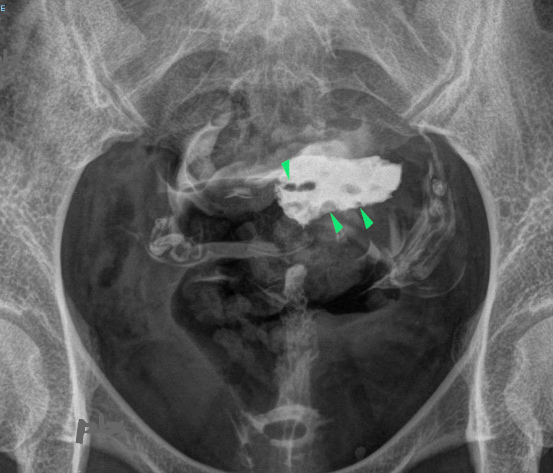

12 – Polypes multiples – Hystérosalpingographie (HSG)

Bilan réalisé dans le cadre d’une infertilité.

Multiples images lacunaires (►), de contours réguliers, moulées par le produit de contraste.